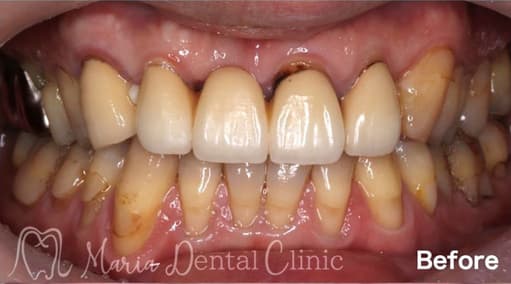

ブリッジの症例

結合組織移植術(CTG)により機能および見た目を改善

前歯のブリッジの見た目の問題と、食べ物が詰まるという2点を主訴に受診された方に、歯肉のボリュームをUPし、機能的、審美的に良好なブリッジ治療を完了した症例です。